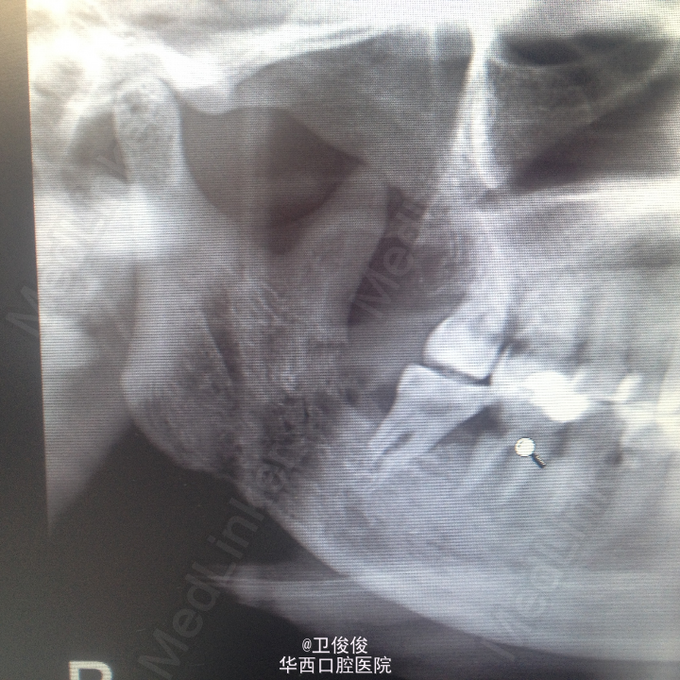

主诉:右侧颌下区有瘘口数周伴流脓 现病史:患者因鼻咽癌行局部放疗,放疗期间右侧后牙疼痛未治疗,数周前出现右侧颌下区皮肤肿胀,自行破溃,一直流脓,口服消炎药,效不佳

查体见:患者右颌下区见一瘘口,有脓血样液体流出, 全景结果是:右侧下颌升支及下颌角区可见骨质有吸收,47可见远中有龋坏。

诊断:放射性骨髓炎 处理:长期换药,待死骨分离